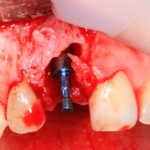

Немедленная имплантация — оптимальное решение в любой клинической ситуации